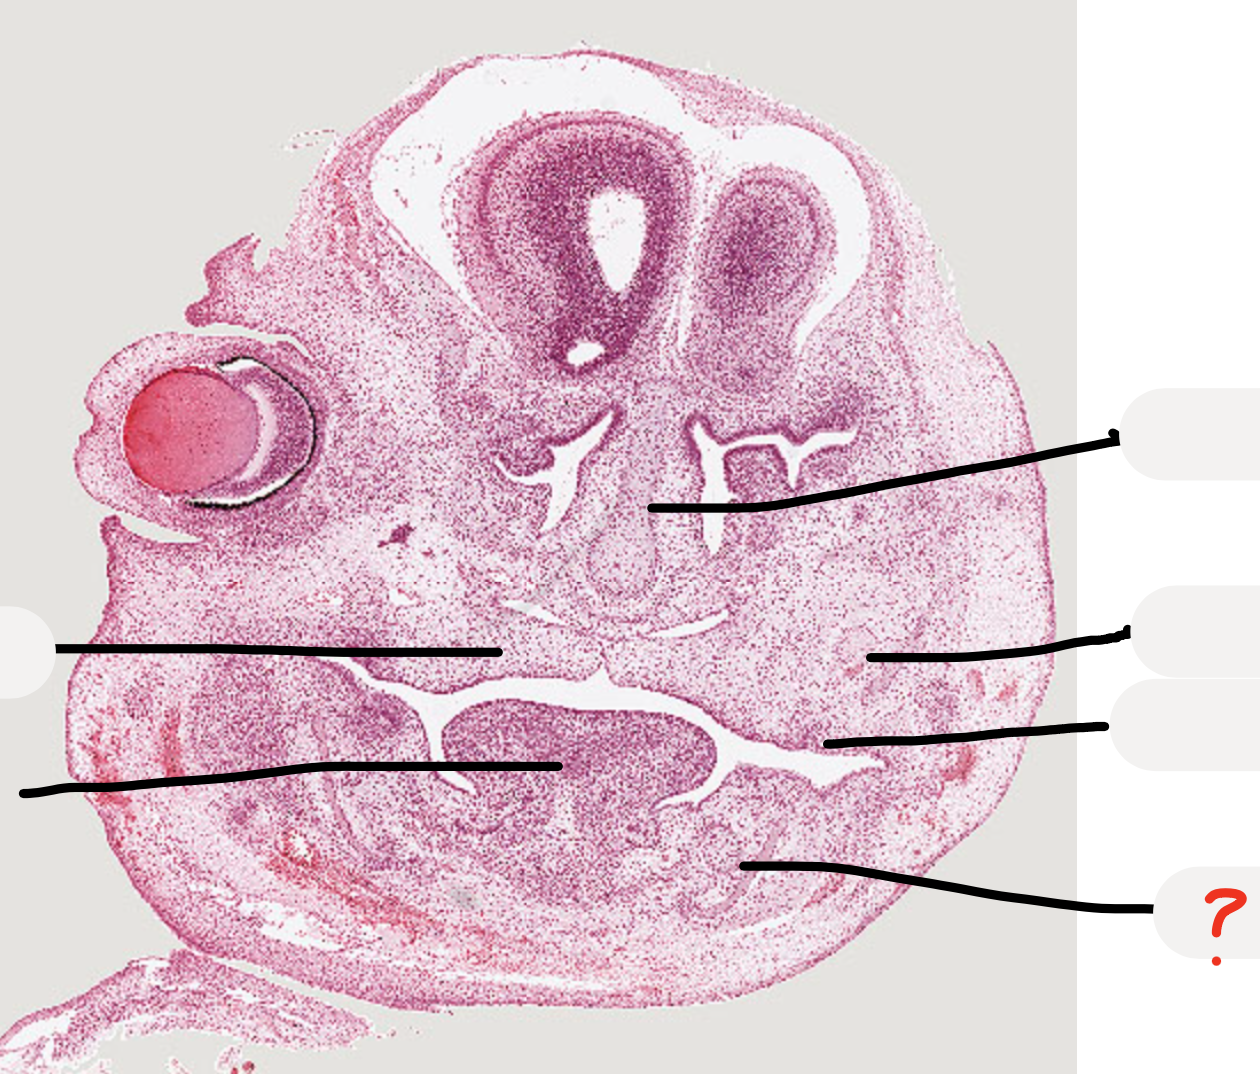

predict what age the embryo is, why?

Week 7 as palatal shelves down lateral tongue and tongue takes up most of the space

Week 6 is when see the first evidence of tooth development

compare the histology of the different structures

mandibular process

maxillary process

developing tooth -> dental lamina and tooth germ

meckel’s cartilage

tongue

palatal shelves

maxillary nerve trunk

early tooth development

nasal capsule